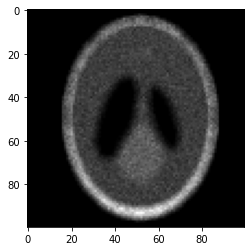

1. Poisson image de-blurring with total variation (TV) regularization [33, 15, 10]. Let the m×n𝑚𝑛m\times n matrix X𝑋X be the true representation of an image, such that each entry Xij0subscript𝑋𝑖𝑗0X_{ij}\geq 0 represents the intensity of the pixel at location (i,j)[m]×[n]𝑖𝑗delimited-[]𝑚delimited-[]𝑛(i,j)\in[m]\times[n], and Xij{0,1,,M}subscript𝑋𝑖𝑗01𝑀X_{ij}\in\{0,1,\ldots,M\}, where M:=2b1assign𝑀superscript2𝑏1M:=2^{b}-1 for b𝑏b-bit images. In many applications, ranging from microscopy to astronomy, we observe a blurred image contaminated by Poisson noise, which we denote by Y𝑌Y, and we wish to estimate the true image X𝑋X from Y𝑌Y. The generative model of Y𝑌Y from X𝑋X is presumed to be as follows. Let 𝖠:m×nm×n:𝖠superscript𝑚𝑛superscript𝑚𝑛\mathsf{A}:\mathbb{R}^{m\times n}\to\mathbb{R}^{m\times n} denote the 2D discrete convolutional (linear) operator with periodic boundary conditions, which is assumed to be known. This convolutional operator is defined by a p×p𝑝𝑝p\times p 2D convolutional kernel with a size q:=p2assign𝑞superscript𝑝2q:=p^{2} that is typically much smaller than the size of image N:=mnassign𝑁𝑚𝑛N:=mn. (For an illustration of the 2D convolution, see [32] for example.) The blurred image Y~~𝑌\widetilde{Y} is obtained by passing X𝑋X through 𝖠𝖠\mathsf{A}, i.e., Y~:=𝖠(X)assign~𝑌𝖠𝑋\widetilde{Y}:=\mathsf{A}(X), and the observed image Y𝑌Y results from adding independent entry-wise Poisson noise to Y~~𝑌\widetilde{Y}, i.e., Yij𝖯𝗈𝗂𝗌𝗌(Y~ij)similar-tosubscript𝑌𝑖𝑗𝖯𝗈𝗂𝗌𝗌subscript~𝑌𝑖𝑗Y_{ij}\sim{\sf Poiss}(\widetilde{Y}_{ij}), for all (i,j)[m]×[n]𝑖𝑗delimited-[]𝑚delimited-[]𝑛(i,j)\in[m]\times[n], and {Yij}(i,j)[m]×[n]subscriptsubscript𝑌𝑖𝑗𝑖𝑗delimited-[]𝑚delimited-[]𝑛\{Y_{ij}\}_{(i,j)\in[m]\times[n]} are assumed to be independent.

is a standard formulation of the total variation. Here we see that (1.5) is an instance of (P)𝑃(P) with f(u):=l=1Nylln(ul)assign𝑓𝑢superscriptsubscript𝑙1𝑁subscript𝑦𝑙subscript𝑢𝑙f(u):=-\textstyle\sum_{l=1}^{N}y_{l}\ln\big{(}u_{l}), 𝒦:=+Nassign𝒦subscriptsuperscript𝑁\mathcal{K}:=\mathbb{R}^{N}_{+}, h(x):=(l=1Nal)x+λTV(x)+ι𝒳assign𝑥superscriptsuperscriptsubscript𝑙1𝑁subscript𝑎𝑙top𝑥𝜆TV𝑥subscript𝜄𝒳h(x):=(\sum_{l=1}^{N}a_{l})^{\top}x+\lambda{\rm TV}(x)+\iota_{\mathcal{X}} where 𝒳={xN:0xMe}𝒳conditional-set𝑥superscript𝑁0𝑥𝑀𝑒\mathcal{X}=\{x\in\mathbb{R}^{N}:0\leq x\leq Me\}, 𝖠𝖠\mathsf{A} is defined by (𝖠x)l:=alxassignsubscript𝖠𝑥𝑙superscriptsubscript𝑎𝑙top𝑥(\mathsf{A}x)_{l}:=a_{l}^{\top}x, l=1,,N𝑙1𝑁l=1,\ldots,N, and θ=l=1Nyl𝜃superscriptsubscript𝑙1𝑁subscript𝑦𝑙\theta=\sum_{l=1}^{N}y_{l}. We note that yl1subscript𝑦𝑙1y_{l}\geq 1 whenever yl0subscript𝑦𝑙0y_{l}\neq 0 for all l[N]𝑙delimited-[]𝑁l\in[N], and hence fθ(𝒦)𝑓subscript𝜃𝒦f\in\mathcal{B}_{\theta}(\mathcal{K}). In Section 4.1 we will discuss how the Frank-Wolfe sub-problem (1.3) associated with (1.5) can be efficiently solved.

We apply our method to the TV-regularized Poisson image de-blurring problem. We present computational experiments that point to the potential usefulness of our generalized Frank-Wolfe method on this imaging problem in Section 4.1.

Outline. The paper is organized as follows. In Section 2 we present and analyze our generalized Frank-Wolfe method for (P)𝑃(P) when fθ(𝒦)𝑓subscript𝜃𝒦f\in\mathcal{B}_{\theta}(\mathcal{K}), using an adaptive step-size strategy that is a natural extension of the strategy developed in [21]. In Section 3 we study the (Fenchel) dual (D)𝐷(D) of (P)𝑃{(P)} and derive and analyze a dual mirror descent method for solving (D)𝐷(D) based on the generalized Frank-Wolfe method for solving (P)𝑃(P). In Section 4 we present computational experiments that point to the potential usefulness of our generalized Frank-Wolfe method on Poisson image de-blurring problems with TV regularization, and we also present computational experiments on the PET problem.